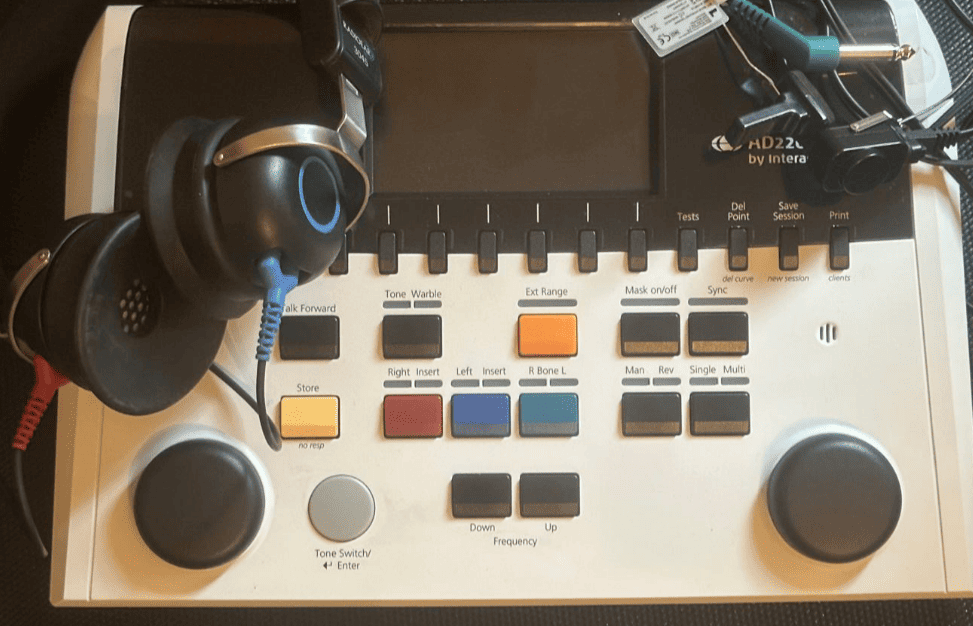

Enregistrement de la voix maternelle

Il est possible d’effectuer un enregistrement de la voix maternelle dans notre centre, ainsi que une évaluation sur votre ecoute qui permet de vérifier si un trouble de l’écoute est impliqué et d’adapter les solutions en conséquence.